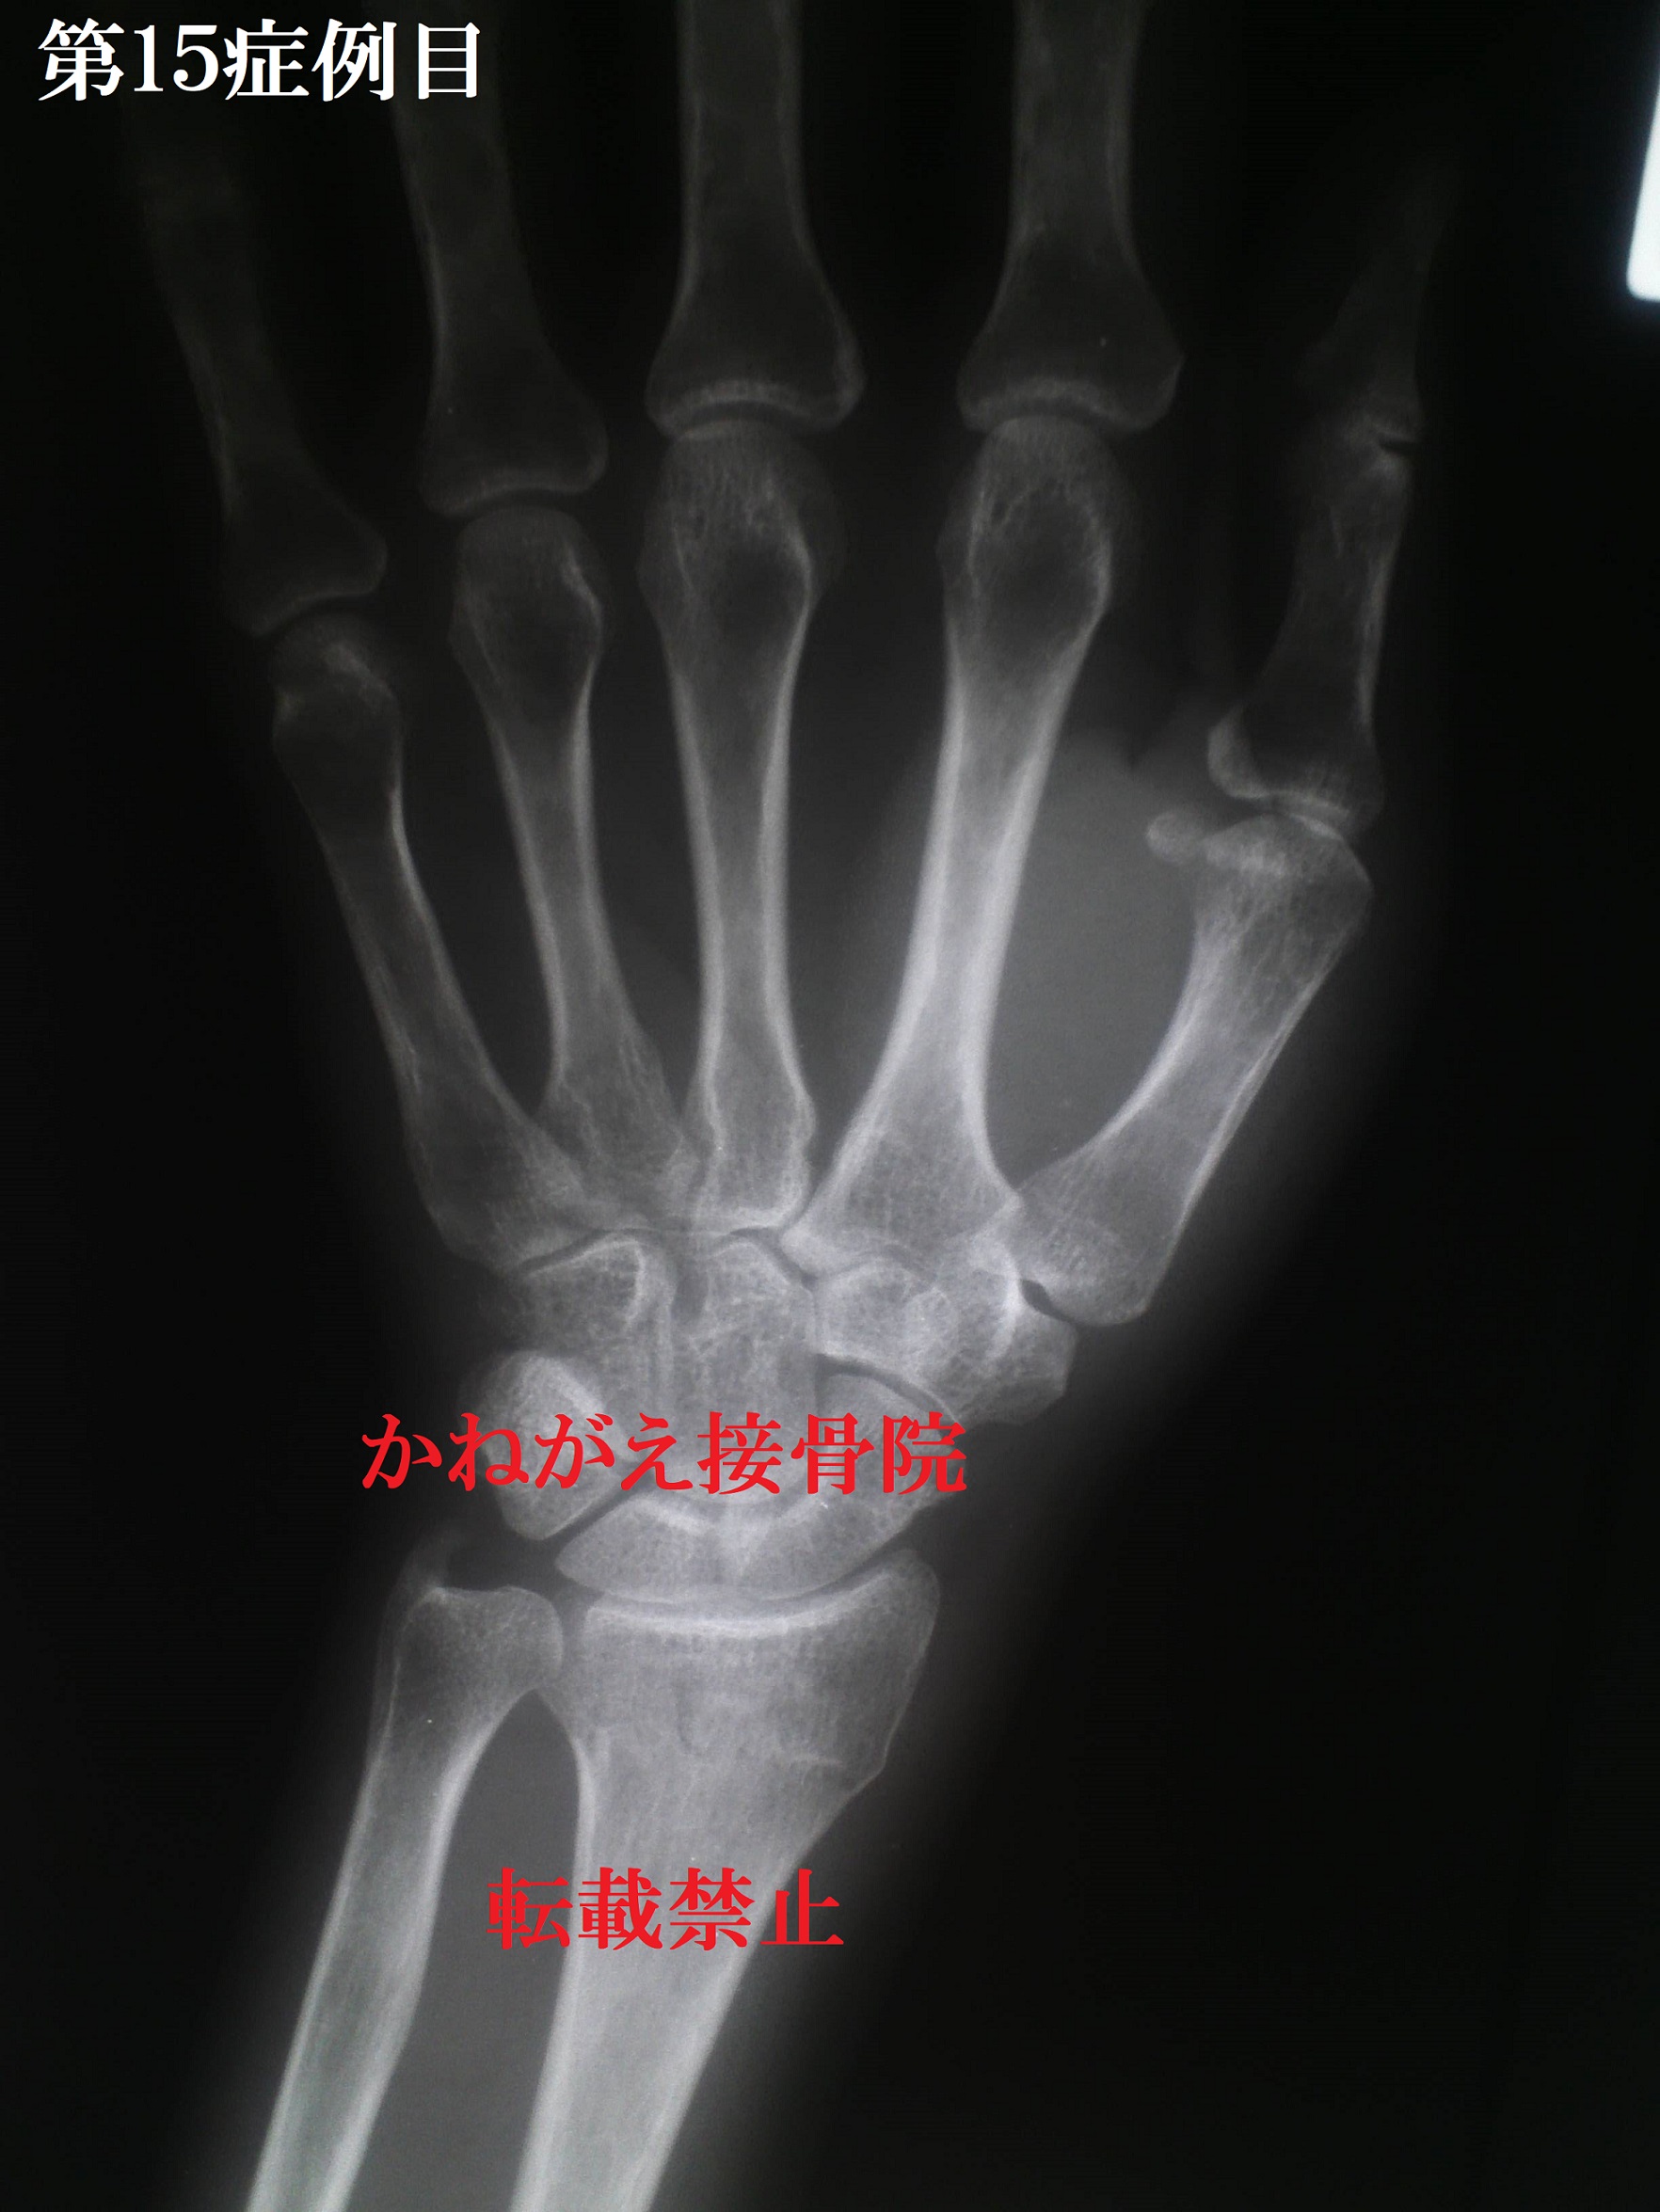

症例15当時54歳 女性

左コーレス骨折

この患者さんは酔っている状態で転倒してしまい 痛みがひかずに翌日に受診され骨折が見つかりま した。 その為受傷後半日経つのですが、やはり患部は腫 れていました。 そして写真でもわかるかと思いますが、骨折の一 般的なイメージとは少し違うように感じたと思い ます。 しかしよーく見ると、橈骨の輪郭がおかしいこと に気が付くと思います。 是非正常な橈骨のレントゲンと比べてみてくださ い。 この方は結構腫れていたために、骨折部の確認が 大変そうだと思ったのを覚えています。 しかし事前にレントゲンで鋭利な断端ではないこ とがわかっていたうえに、限局性圧痛が顕著だっ た為、意外と簡単に骨折部を把握することができ た症例です。 骨折部の確認ということで、少し脱線しますが、 我々柔道整復師はレントゲンが扱えません。 そのためこの「骨折部の確認」が非常に重要とな ります。 骨折部の確認は原則として健側があるなら健側と 比較しながら見ていきます。 まず訴えのある部位の全体の形をみて、それぞれ の骨指標から変形転位の方向を確認します。(こ れを怠ると触って確認するときに大変なことにな る場合があるので、たとえ受傷機序から骨折名が 推測できたとしても必ず全体を見てください) 実際にコーレス骨折の受傷機序なのにレントゲン で確認するとスミス骨折だったということはよく あることです。 そして全体の変形した外観と、それぞれの骨指標 の位置異常を確認することで、患部のどこが凸で どこが凹なのかということがわかります。(これ はレントゲンを取らなくても把握することができ ます)。 この凹凸の判断までできた場合は、ほぼ確実に骨 折していると判断する事ができます。 また、変形があまり無い骨折だったとしても、骨 折の固有症状というものがあるので、折れている のかどうなのかということは、ある程度判断する 事ができます。 話を戻しまして、今回の骨折の症状は 限局性圧痛(++)、腫脹(+) 皮下出血(+) 神経・大血管損傷(−)、皮膚損傷(−) 転位(±)→短縮(+)、背屈(±) 特筆すべき持病などはなし だったので整復しました。